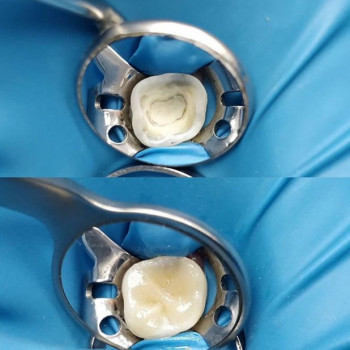

| Установка пломби | |

| Установка фотополімерної пломби | |

Екатерина мне очень понравилась как мастер, потому что она все спокойно объяснила, рассказала что можно установить и какое время займет на лечение. Я выбор сделала и все рекомендации забрала на вооружение. Очень понравился результат. Эстетичный вид зуба сохранился.